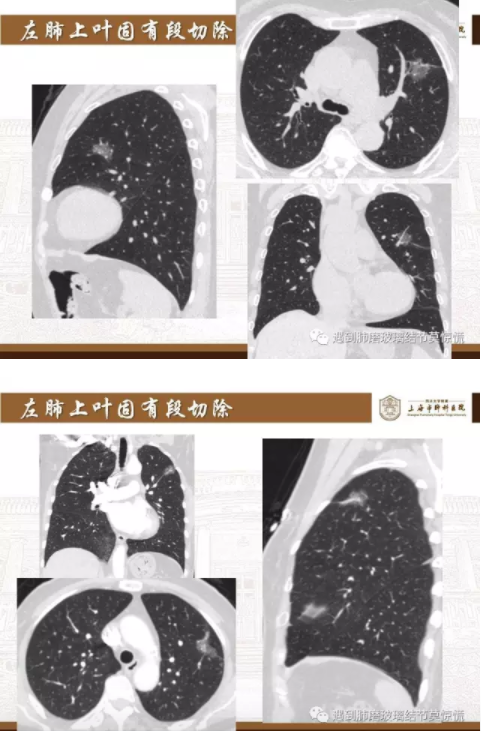

下面就我们的病例分析一下怎么进行肺段切除。

MIA= 微浸润腺癌   IA= 浸润性腺癌   AIS= 原位腺癌   AAH= 不典型腺瘤样增生